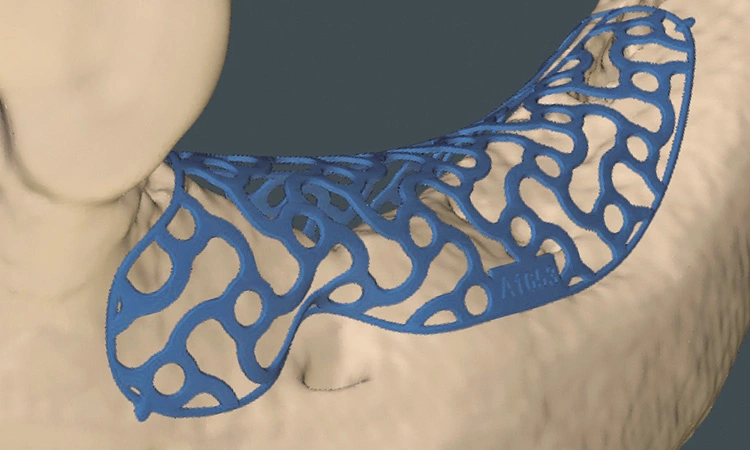

Präoperativ wurde im Sinne eines Backward Planning erst die spätere Implantatposition und in Kenntnis dieser, die Ausdehnung des Titangitters festgelegt. Hierbei wurde festgestellt, dass sich zum einen das Foramen mentale direkt im Augmentations- und Implantationsbereich befindet und zum anderen der Verlauf des Nervus alveolaris inferior, trotz Augmentation, nur relativ kurze Implantate zulassen wird.

Bei der digitalen Planung des Gitters wurde dieser Aspekt besonders berücksichtigt und zudem auf die Lage des Foramen mentale speziell geachtet. Das Gitter wurde im Austrittsbereich ausgespart, um eine Traumatisierung zu vermeiden (Abb. 4-19).